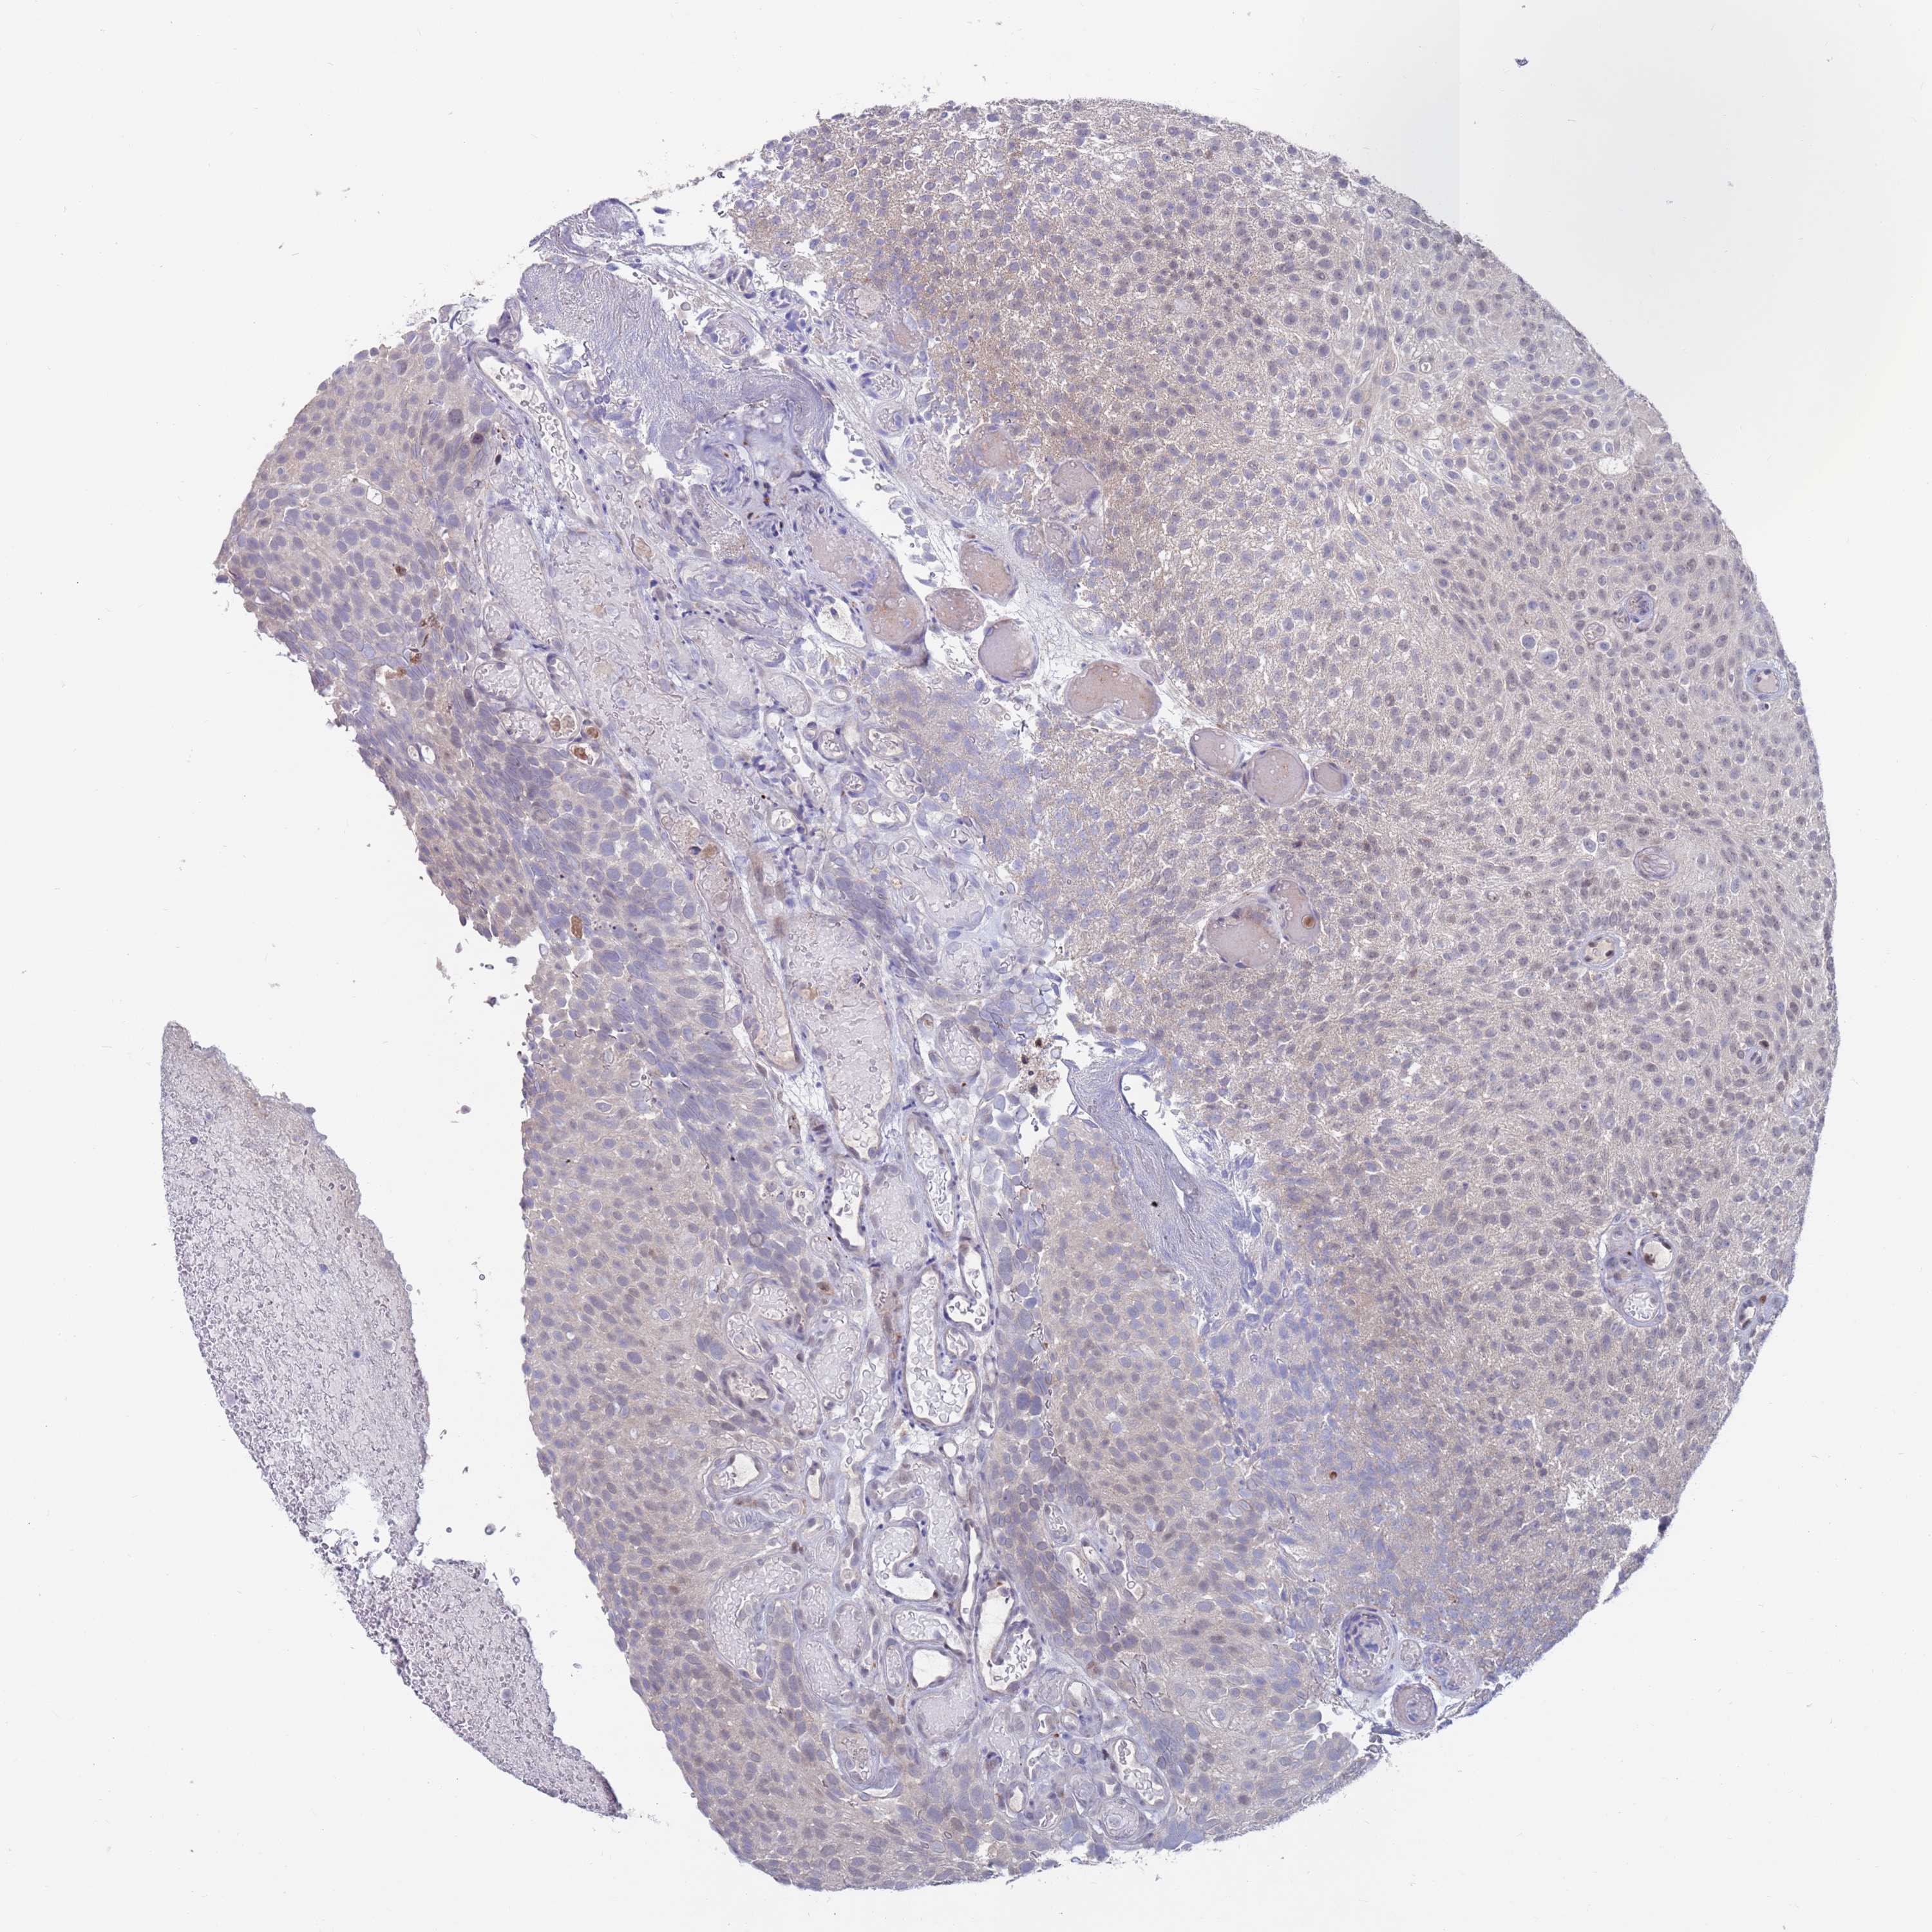

UROTHELIAL CANCER - Protein expressioni

A mouse-over function shows sample information and annotation data. Click on an image to view it in a full screen mode. Samples can be filtered based on level of antibody staining by selecting one or several of the following categories: high, medium, low and not detected. The assay and annotation is described here.

Note that samples used for immunohistochemistry by the Human Protein Atlas do not correspond to samples in the TCGA dataset.

Antibody stainingi

Antibody staining in the annotated cell types in the current human tissue is reported as not detected, low, medium, or high, based on conventional immunohistochemistry profiling in selected tissues. This score is based on the combination of the staining intensity and fraction of stained cells.

Each image is clickable and will lead to virtual microscopy that enables deeper exploration of all samples and also displays staining intensity scores, fraction scores and subcellular localization as well as patient and tissue information for each sample.

Antibody HPA046800

Staining

High

Medium

Low

Not detected

Intensity

Strong

Moderate

Weak

Negative

Quantity

>75%

75%-25%

<25%

None

Location

Nuclear

Cytoplasmic/membranous

Cytoplasmic/membranous,nuclear

Urothelial carcinoma, High grade

Urothelial carcinoma, Low grade